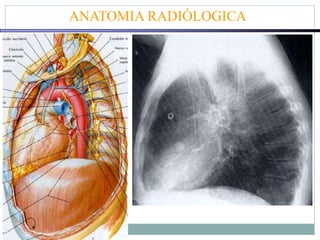

ANATOMIA RADIÓLOGICA